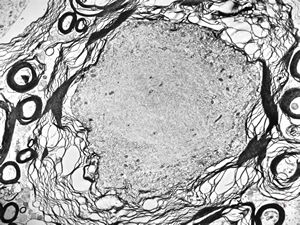

F,2y. | normal n. suralis